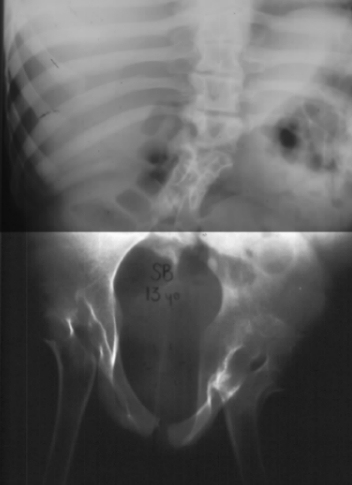

Patient with multiple abnormalities with short trunk correlated with

the degree of lumbar agenesis; marked atrophy of the buttocks showing gluteal

dimples with short intergluteal fold, and horizontal anus. Characteristically

severe atrophy of the lower limbs with an appearance similar to that of

distal arthrogryposis; the lower extremities are in flexion, abduction,

and external rotation contracture at the level of the hips, and usually

there is a severe flexion contracture of the knees giving the classic Buddha-like

position often described. However, the appearance of the patient is directly

correlated with the degree of lumbosacral spinal involvement.

LOWER EXTREMITIES:

- frequently, hips have a flexion, abduction and external rotation contracture.

Sometimes, the hips are dislocated secondary to pelvic obliquity and/or

the acetabula reorientation